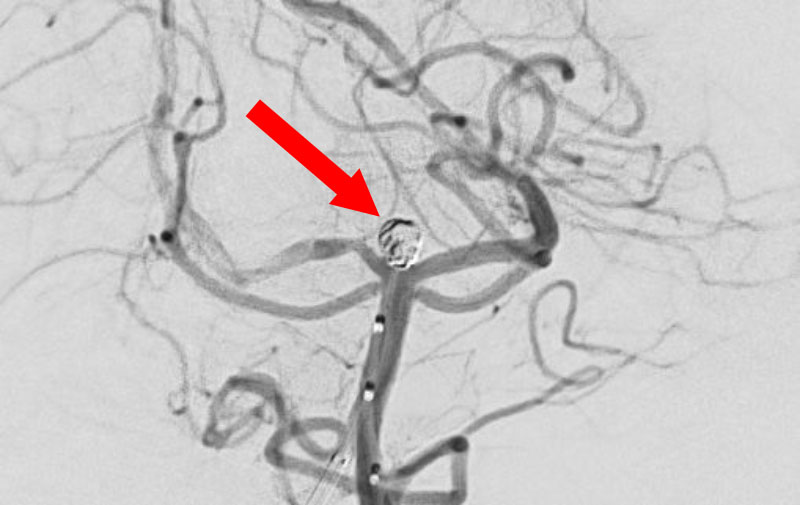

No.1631 手術中